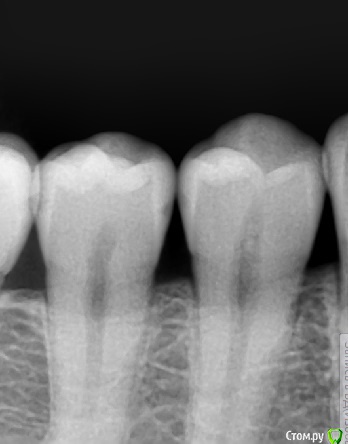

Zlata-doctor Опубликовано 4 июня, 2015 Поделиться Опубликовано 4 июня, 2015 Я бы лечила, рентгенологически там уже есть полости и не факт, что только в пределах эмали. Видео не понравилось тоже по тем-же соображениям, о кот писала Джима. Ссылка на комментарий

Kolchanov Опубликовано 12 апреля, 2016 Автор Поделиться Опубликовано 12 апреля, 2016 Почти год спустя те же зубы 3 Ссылка на комментарий